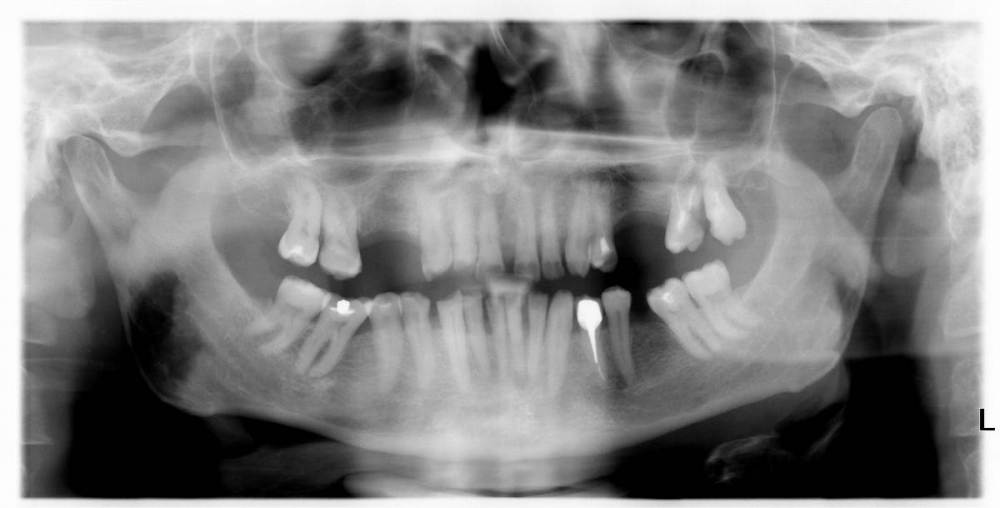

GENRY Опубликовано 6 сентября, 2021 Поделиться Опубликовано 6 сентября, 2021 Здравствуйте! Как лучше восстановить ( пусть частично) 28 зуб? Удаление не желательно т.к. с имплантацией связываться не хочу (синус лифтинг.. возраст 75 лет...) ,а опор для ортопедических конструкций нет. Кроме того боюсь, что в процессе удаления будет разрушена пломба 27 _го. Оптимизма добавляет история 27 го На орто 2012г показан 27 до его восстановления и до вмешательства в 28 зуб с добавлением в него пломбы в 2012г . Канал 28_го (небный ?) был уже запломбирован кем то раньше, скорее всего резорцин-формалиновой пастой) Доктор в 27 - м обнаружил на снимках 3 канала, наполовину прошел небный и полностью прошел дистально- щечный канал с наполнением их горячей гуттаперчей . Поскольку устье 3_го канала обнаружено не было, восстановил 27 зуб 2_мя стекловолоконными штифтами с использованием Build-It . Дистальную стенку сделал, кажется на основе пасты СПЕКТРУМ . К дальнейшей судьбе 27_го доктор отнесся скептически ( не более 2_х лет!), но похоже сработал надежно, пошел уже 10_й год, а 27 все стоит. Но 10 мес. назад выпала пломба 28 _го и он принял вид показанный на снимке. Не беспокоит. Хотелось бы повторить историю с 27_м, т.е. восстановить 28 по типу 27_го .... думаю мне хватит 5_7 лет... Регулировать нагрузки на этой стороне челюсти я научился. Сделал КТ сегмента 27_28 (В Пикассо, Vatech, просмотрщик EZ3D2009 plus ) но не смог найти ( сейчас живу в Феодосии ) терапевта работающего с этой программой. Кто то вообще не использует никакие КТ (но при этом берется за восстановление штифтом без перелечивания каналов) , кто то готов к перелечиванию, но полагается только на свои мануальные навыки, игнорируя КТ или формально глянув на пару проекций. На последней консультации добился 4-х снимков из КТ, но в общем то случайных и скорее всего не показательных.. Выкладываю скриншоты... Понял, что надо выходить за пределы городка и расширять собственное (к сожалению) понимание возможных вариантов лечения и их последствий. Вопросы по 28: 1. Если хотя бы один канал запломбирован (видимый на снимке) то это автоматически означает вскрытие камеры , а значит вскрытие и убитость содержимого (нервов, сосудов) всех остальных каналов , поскольку их устья на дне камеры? (Да, Нет, Другое) 2. Если Да, то нормально ли было пломбировать 28, не найдя и не залечив (с пломбировкой) другие каналы одновременно с небным (я имею ввиду сейчас самую раннюю пломбировку, до представленного орто) 3. Поскольку пломбировки всех каналов (сколько их ?) точно не было, то за эти 10-15 (?) лет (уже сейчас зуб стоит открытым почти год (ковид, консультации..)) должен развится пульпит, периодонтит... ? Или не обязательно? Ничего не болело, никаких выделений не было 4. Есть ли признаки какой либо хроники, воспалений в тканях на снимках? 5. Если ткани зуба и около него в порядке, то может не обязательно перелечивать все каналы, чтобы не ослаблять зуб? А только те, в которые будут вставлены штифты? Вкладка, похоже исключается т.к. феррул не замкнут на стыке с 27 зубом. 6. Есть ли какие либо оценки минимального количества требуемых штифтов ? 7 . Поскольку за 4 консультации я так и не получил ответов и снимков срезов (по КТ )показывающих количество и топологию корней и каналов, то придется добывать эту информацию самому. Буду благодарен за ссылки на материалы показывающих как это делается т.е. в каких из 3 проекций, при каком положении осей и.т.п. Я нашел только хороший ролик Ервандяна А.Г., но мне недостаточно, не хватает знания топологии зубов. Спасибо за внимание. Ссылка на комментарий

dentikl Опубликовано 6 сентября, 2021 Поделиться Опубликовано 6 сентября, 2021 (изменено) нет.Присутствие "вылеченного" 28 зуба может привести к суставной патологии.Зуб нужно удалять. Во рту отсутствует 7 зубов.Несколько депульпированных восстановлены пломбами.Прийдите на очный прием к ортопеду-он составит план реабилитации. Изменено 6 сентября, 2021 пользователем dentikl Ссылка на комментарий

GENRY Опубликовано 6 сентября, 2021 Автор Поделиться Опубликовано 6 сентября, 2021 Поясню свое стремление сохранить 28-ой, похоже здесь "возрастное" непонимание. Мне 75 т.е. согласно статистике для мужчин из РФ, в среднем осталось жить лет 6. Зубы еще год назад как то работали (пусть и с патологиями, нарушениями механики и.т.п.)..приспособился. Если бы такое состояние продолжилось еще 6 лет _ меня бы устроило.. Т.е вопрос для меня не в том, чтобы все в этом углу соответствовало стоматологическим канонам, а можно ли вернуться к состоянию : год назад? В 2012 был снят кусок 28 _го, примыкающий к 27 _му (наверное мешал реставрации 27_го) и заменен пломбой. Каналы не трогались. Вряд ли они были герметизированы этой пломбой от среды, кроме одного _запломбированного. Но зуб простоял 9 лет. 10 мес. назад эта пломба выпала. Возможно за эти годы в системе среда _каналы_кость ничего не изменилось и простое добавление пломбы (со штифтами или без) вернет зуб в прежнее состояние и я спокойно уйду с ним в мир иной. Меня это устроит. И не надо мне в этом случае ни удаления. ни имплантов, ни ортопедов. А может в системе среда _каналы_кость уже произошли изменения (инфицирование, хроника, воспаления и.т.п ) и такой вариант не прокатит? И это уже видно по снимкам? Тогда другое дело...здесь и возникают удаления. импланты, ортопеды. А может еще этих изменений нет, но они могут возникнуть при препарации...прохождении каналов (может они зацементировались сами?, а мы их вскроем)... и.т.п. Тогда как снизить риски такого развития событий? Для выяснения , какая ситуация имеет место, и нацелены мои вопросы.. Ссылка на комментарий

GENRY Опубликовано 8 сентября, 2021 Автор Поделиться Опубликовано 8 сентября, 2021 12 часов назад, dentikl сказал: покажите плз фото нижних и верхних передних зубов.Можно телефоном.Верхние-чтобы увидеть режущий край (если он сохранен) Представленная раньше орто сделана в 2012г. Произошли изменения: 11,21,22 - живые с коронками; 12 - коронка на вкладке; 24 - был треснут, эндопролечен (фото прилагается), восстановлен; 13,23 - живые, но сильно стерты, особенно у десны . Займусь ими после разборки с 28 (и 18). они стоят открытые, На 17 одета металлическая коронка. 18 лишился пломбы 2 мес. назад. На след. неделе еду на его лечение. Снимок 17,18 перед лечением в 2013 _ прилагаю Ссылка на комментарий